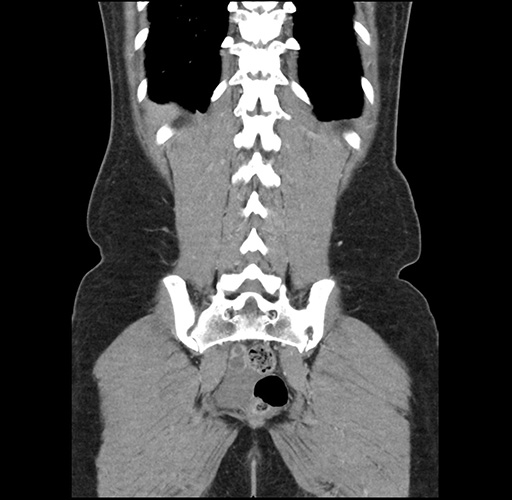

Imaging Analysis

Look through the patient's CT scan to identify any areas of concern for the necessary procedure.

Based on your CT findings, which issue(s) would give reason for "planned slowing down moment(s)" in this case?